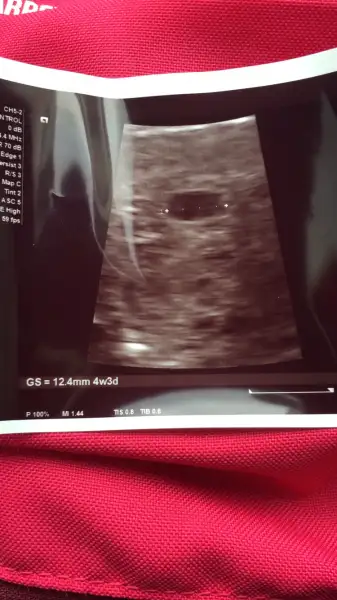

Aa bana verilen ultrason kağıdında yazıyır mu acaba hiç onu unuttum[/QUOTEyazıyor canım

yazıyor canım bak ultrason kağıdının altında 12.4 mm diye :)Aa bana verilen ultrason kağıdında yazıyır mu acaba hiç onu unuttum